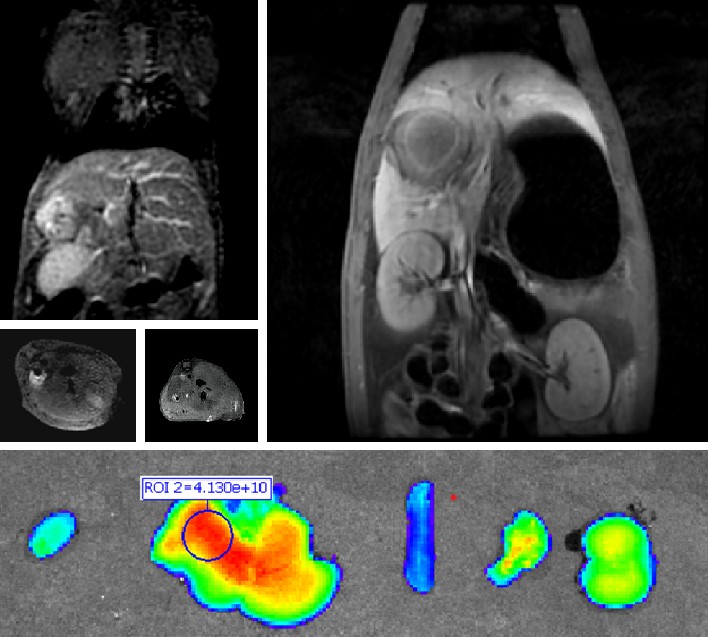

mg电玩娱乐在线网址自主研发双模态造影剂PL002,首次提出通过整合磁共振技术,弥补现有荧光染料假阳性率高、透射深度有限等的短板,进而提升手术的精确性,降低手术过程中的风险,是全球首个获批临床试验的荧光/磁共振双模态造影剂,目前也已经获得美国FDA临床试验批件。